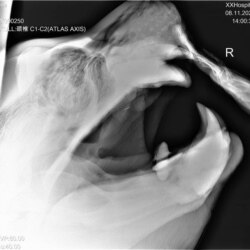

Обученный зверь по команде замер на несколько секунд и позволил сделать себе снимок челюсти

Светлана – кипер, рабочий по уходу за животными. Она уже два года проводит тренинги с гигантским зверем: вместе с коллегами чистит сивучу зубы, промывает ротовую полость, учит несложным командам. Это не дрессура ради шоу – благодаря занятиям животное привыкает к людям и позволяет проводить с ним различные манипуляции, прежде всего, медицинские. Недавно сивучу сделали рентген: обученный зверь по команде замер на несколько секунд и позволил сделать себе снимок челюсти переносным аппаратом.

– Дается команда, сотрудники прикасаются к носу и нижней челюсти сивуча, как бы фиксируют его голову. Мы не держим его, а даем ощущение контакта. Так и получилось сделать снимок, – рассказывает Светлана.

Снимок зубов Кима

Рентген показал проблемы с клыками и в целом с верхней челюстью. По словам Светланы, у старенького сивуча и так осталось четыре зуба вместо 25-ти. Но особого дискомфорта ему это не доставляло – рыбу сивучи не жуют, а заглатывают. Недавно воспаление перешло на костную ткань.

– Мы можем сказать: периодонтит и пульпит верхних клыков, пародонтит возле верхних и нижних клыков. Для более точных диагнозов нужно делать еще снимки, но это технически невыполнимо, потому что мы не можем расположить аппарат под нужным углом из-за решеток. Также есть подозрение на остеомиелит верхней челюсти, – говорит главный ветеринарный врач зоопарка Алла Тыкманова.